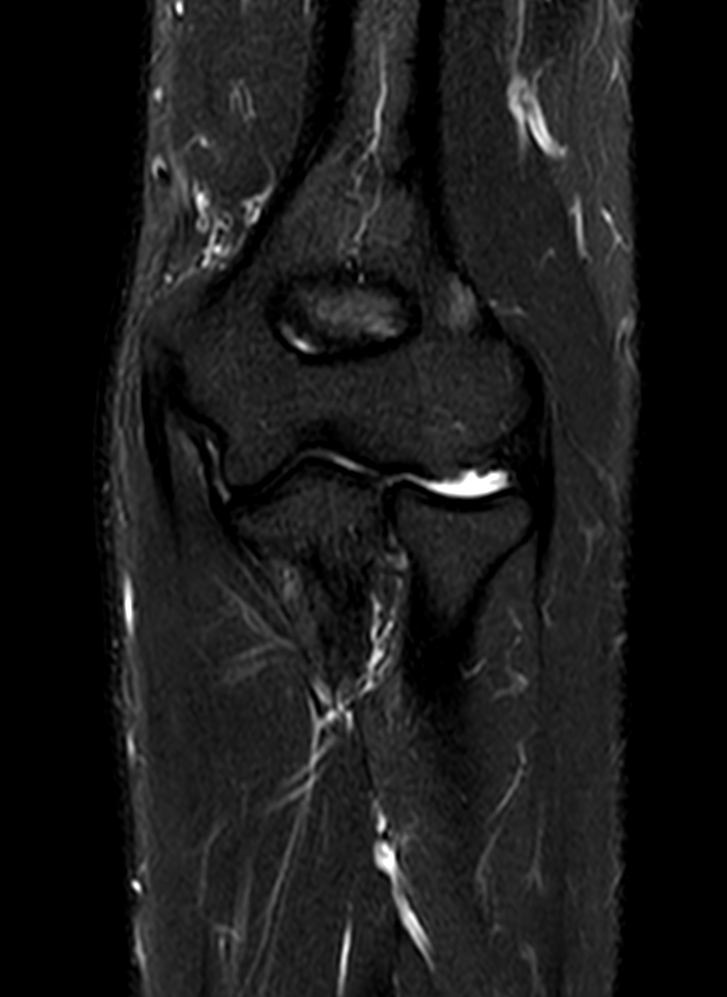

High quality Elbow imaging with Compressed SENSE

Spital Uster, Switzerland